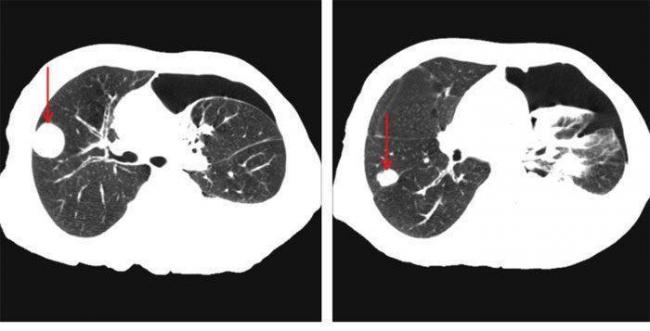

Очаговые изменения

Очаговые изменения в лёгких могут быть разного размера. Очаги мелкого диаметра 1-10 мм выявляются при различных диффузных патологиях лёгочной ткани. Очаги с высокой плотностью и довольно чётки краями в основном наблюдаются в интерстиции лёгкого. Различные очаги низкой плотности, напоминающие матовое стекло, с нечёткими контурами возникают при патологических изменениях в респираторных отделах дыхательных органов.

- Центрилобулярные очаги. Наблюдаются в артериях и бронхах или в непосредственной близости от них. Они могут быть довольно плотными, хорошо очерченными и однородными. Изменения лёгочной ткани такого типа наблюдаются при пневмониях, эндобронхиальном туберкулёзе и разных видах бронхита, преимущественно бактериального происхождения. Есть и другой тип центрилобулярных очагов, в этом случае лёгочная ткань имеет мелкие уплотнения и похожа на матовое стекло.

- Периваскулярные очаги – это патологические образования, которые находятся в непосредственной близости от кровеносных сосудов. Такое состояние наблюдается при онкологических патологиях и туберкулёзе. Очаги могут быть как единичные, так и множественные.

- Хаотично расположенные очаги. Такие образования характерны для патологических гематогенных процессов. Это может быть гематогенная инфекция, туберкулёз или метастазы гематогенного типа. Большие множественные очаги, размером около 10 мм, частенько наблюдаются при септических эмболиях, гранулематозе, грибковых инфекциях и метастазах. Все эти заболевания имеют некоторые отличия, по которым их можно дифференцировать.

Как выглядят метастазы в легком на КТ?

Метастазы в легких на КТ Лимфогенные метастазы легких на КТ выглядят как множественные мелкие диссеминированные очаги. Они расположены вдоль междольковых перегородок и плевры. Картина напоминает туберкулез и саркоидоз, и в этой связи часто требует уточнения.